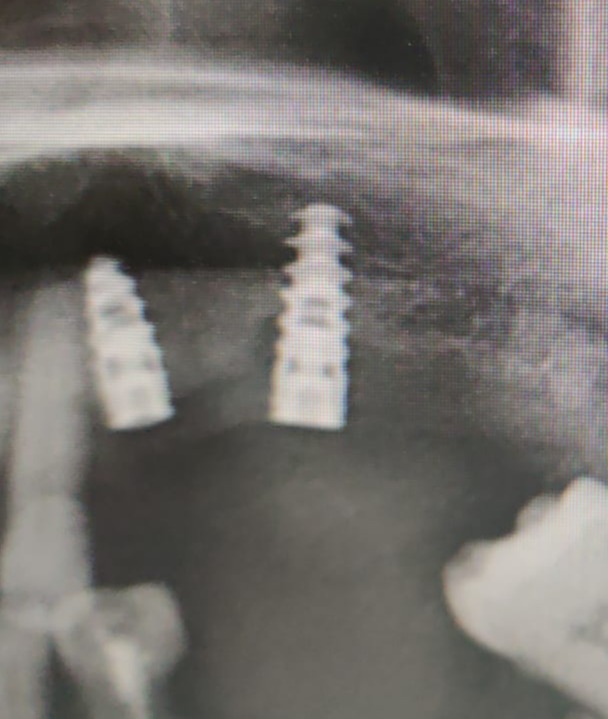

Satisfactory x ray.